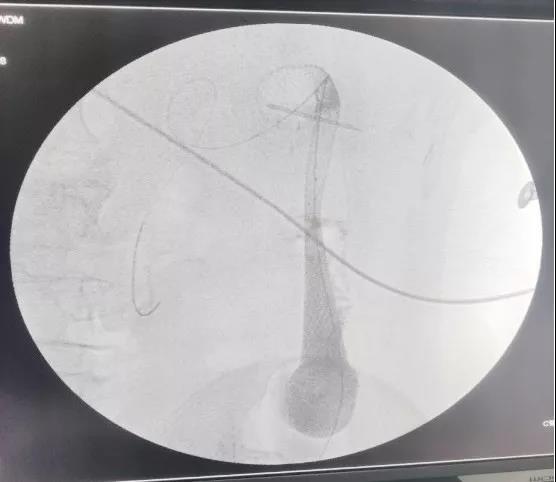

经过周密策划、积极准备,手术当天在消化内科刘健医生肠镜引导下将导丝送至目标位置,后经导丝引入导管,拔出导丝后分别在狭窄区近远端造影,证实靶区准确无误后,再置入导丝通过结肠狭窄段,成功置入肠道支架。

(术中置入肠道支架)